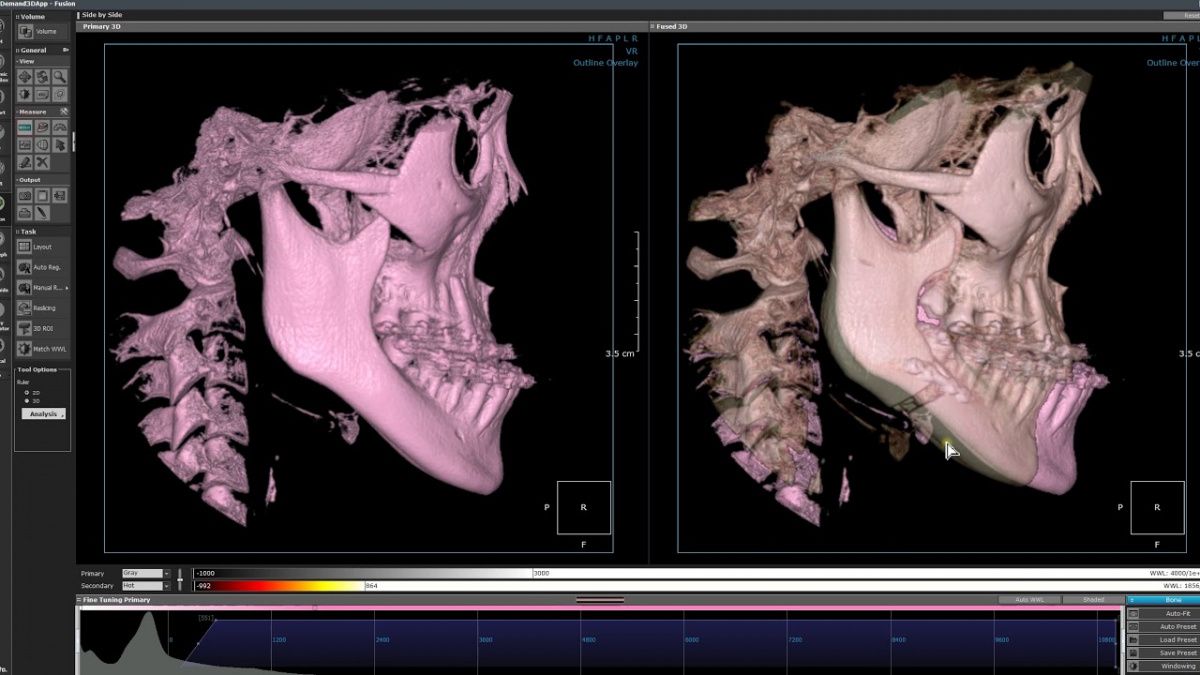

Немаловажным, а может главным вопросом, является универсальность программы-просмотровщика, в которой будут работать врачи-стоматологи. У Papaya 3D есть два варианта программ: Triana и OnDemand3D. Оба просмотровщика обладают схожим интерфейсом и имеют самые важные опции, а именно:

• режим MPR (многоплоскостная реконструкция). Именно здесь выстраивается интересующий участок челюсти или зуба для анализа.

• панорамный реформат. Возможность постройки классической и сегментарной панорамы позволяет продемонстрировать план лечения пациенту, а также оценить расположение анатомических структур на боковых кросс-секциях.

• модуль дентальной имплантации. Возможность виртуальной установки дентального имплантата с анализом окружающей костной ткани. В библиотеке представлен широкий спектр имплантологических систем с индивидуальной прорисовкой имплантата.

• выделение нижнечелюстного канала позволяет продемонстрировать расположение важного анатомического образования и определить зону безопасности при проведении лечения.

• функции плотности, линейных измерений и угла – необходимы для получения полноценной информации для последующего лечения.

• 3D режим – показывает трехмерную модель челюсти с целью определения аномалий, деформация, а также визуализации виртуальных имплантатов.

Таким образом обе программы являются простыми в пользовании, но обладающими обширным спектром возможностей для диагностики любыми специалистами-стоматологами. В данные программы происходит загрузка классических файлов DICOM 3.0, которые являются общепринятым форматом записи данных пациента. Это важный момент, так как позволяют врачу, имеющему полную версию программы загружать даже сторонние исследования и просматривать их в этих программах. Простота в освоении этих программ позволяет даже специалисту, не работающему раннее с этими программами, быстро адаптироваться и получить качественную информацию. Возможность выгрузки STL-файла дополнительно создает возможность интегрировать данные с цифровым ортопедическим протоколом.